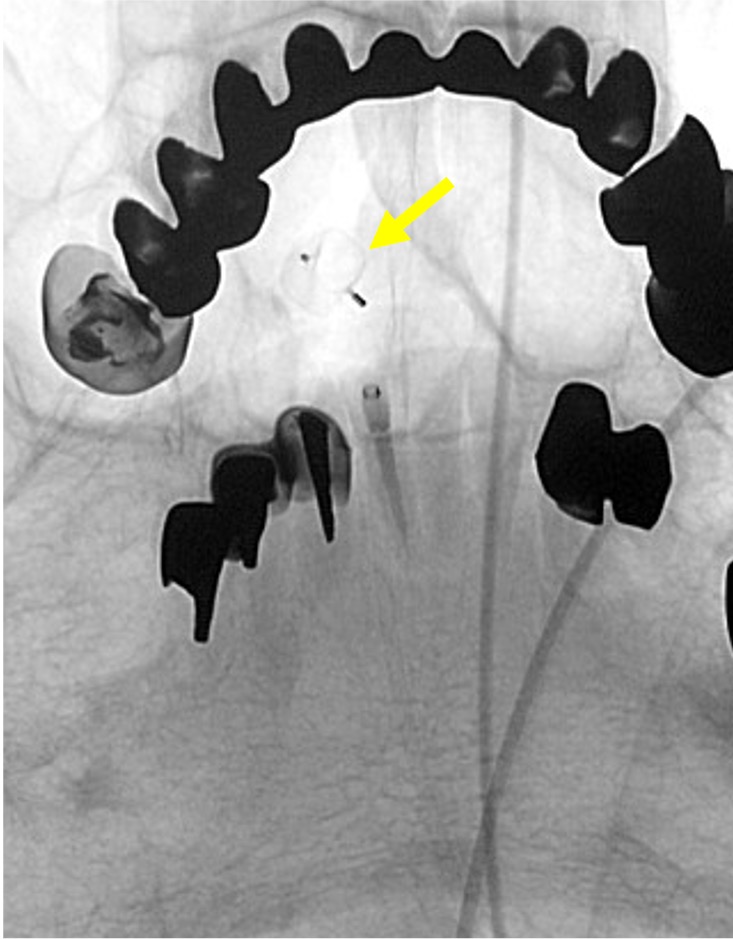

当院で行われた症例を提示いたします。80歳、女性、くも膜下出血の患者様。血管撮影にて図1〜4赤矢印の様に脳底動脈に広頸のネックを伴う不整形の瘤を認めました。母血管の蛇行狭窄が強く、マイクロカテーテルが複数入りにくい状態だったのでWEB(図5〜8黄色矢印)を用いて治療を行いました。術後MRAでも図10青矢印の様に動脈瘤は描出されません(図9は術前MRA)。現在も出血なく経過しております。

図5 |

図6 |

図7 |

![]() 図8 |